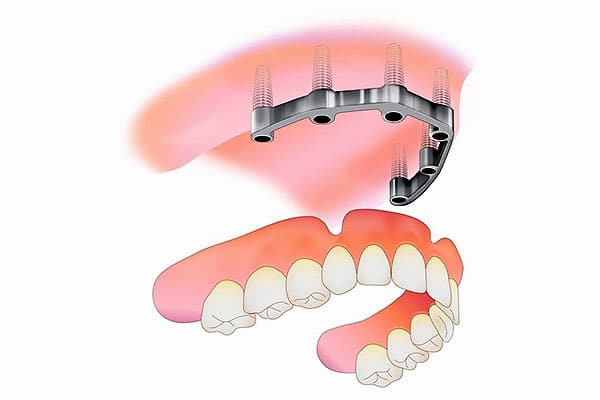

Implant retained on a bar, upper full complement of teeth

For a full arch of upper dentures, there are usually four implants inserted, but again, this number will be subject to the outcome of our clinical assessment.

Small, surgical-quality, titanium ‘screws’ is the best way to describe implants. We are effectively mimicking the function of natural teeth roots where teeth are missing. Once screwed in, the implants fuse with your jawbone. Devices called abutments are then fixed to the top of the implants that hold the specially designed denture.

Implants are an incredibly versatile dental ‘tool’. They can be used in different combinations to support a single tooth, several teeth or a complete set of teeth as with our dentures.